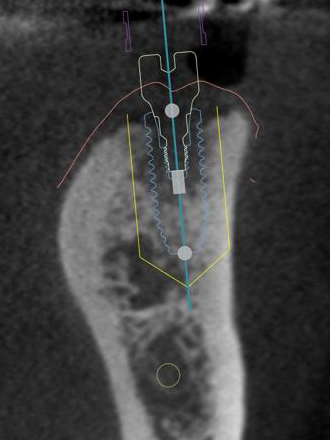

当院ではインプラントの手術前に必ずCT撮影を行い、骨の状態や重要な神経の位置の精査をします。この精密検査を行うことによりインプラントの埋める方向や深さの安全性を事前に確認することができます。

実際の手術を行う際にはサージカルガイドを用いることにより、事前に計画したインプラントの埋める方向や深さと誤差が無い正確な手術を行っております。

サージカルガイド

インプラント手術のシュミレーション